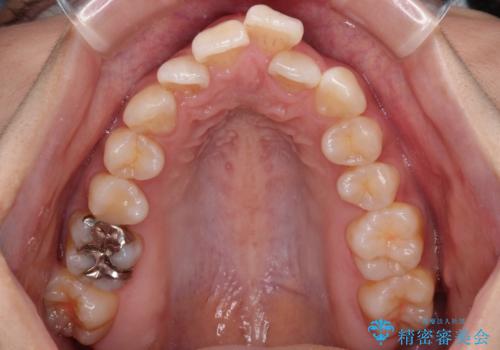

スッキリとした口元へ 出っ歯の抜歯矯正

- 上下の出っ歯を気にして来院された患者様です。

口元を積極的に引っ込めるために、上下左右の第一小臼歯を4本抜歯することとしました。

最終的には上下の正中も合い、横顔の印象が変わるほどスッキリとした口元となりました。